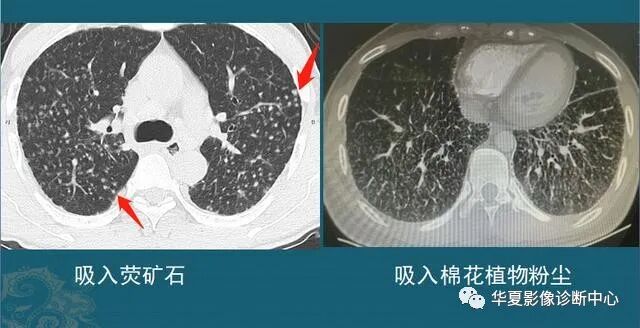

吸入粉尘,形成良性小结节